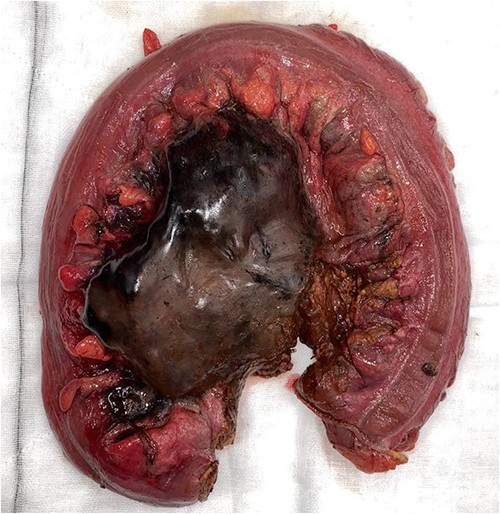

On CT of her abdomen and pelvis, there was a large volume of pneumoperitoneum and a massive sigmoid faecaloma suggestive of stercoral perforation associated with ischaemic changes (Fig. 1). She underwent emergency laparotomy, which identified a grossly dilated and redundant sigmoid colon impacted with a large, inspissated faecaloma >15 cm in diameter (see Figs 2 and 3). The perforation was identified in the mid to distal sigmoid colon with evidence of necrosis of the wall. A Hartmann’s procedure and extensive washout was performed. Post-operatively, the patient required vasopressor support for septic shock in intensive care, as well as granulocyte colony stimulating factor (G-CSF) to help in the management of her febrile neutropaenia. Her Clozapine was suspended for several days due to her neutropenia. She was given G-CSF to improve her neutropenia to improve her chances of survival as it known that immunocompromised patients with sepsis have worse prognosis [9]. Fortunately, the patient recovered well post-operatively and was discharged to rehabilitation on day 10.

CT abdomen pelvis demonstrating inspissated with faecaloma with pneumatosis and adjacent free gas.

In this case, the patient met all four criteria. Furthermore, Fig. 1 clearly shows that the pressure effect from an impacted inspissated faecaloma can cause necrosis of the bowel wall in the absence of diverticulitis, neoplastic lesion and adhesions as the adjacent bowel was healthy without other disease processes. This case report supports that stercoral perforation from chronic constipation is a real entity. The old adage that constipation can kill is not a myth.